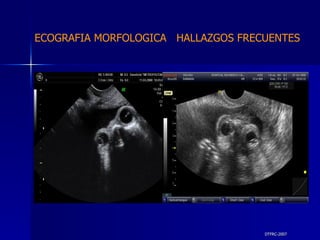

DTFRC-2007 ECOGRAFIA MORFOLOGICA  HALLAZGOS FRECUENTES   MATERIAL Y METODO ES UN ESTUDIO DESCRIPTIVO, RETROSPECTIVO  DE ESTUDIO ECOGRA FICOS REALIZADOS ENTRE MARZO 07 A MARZO 08 EQUIPO DE ALTA RESOLUCION   VOLUSON 730 PRO  MEDISON SA 8000 live MEDISON SA 8000SE CRITERIO DE INCLUSION:   POBLACION GENERAL    GESTACIONES  20 a 24 SEMANAS   UNIVERSO  N 211

DTFRC-2007 ECOGRAFIA MORFOLOGICA  HALLAZGOS FRECUENTES   Sistema Nervioso Central  8  Cardiovascular  0 Genitourinario  6 Musculos Esqueleticos  2 Gastrointestinales  2  Otros  12  Total  30   NUMEROS DE ANOMALIAS POR SISTEMA n N  211

DTFRC-2007 ECOGRAFIA MORFOLOGICA  HALLAZGOS FRECUENTES   SISTEMA NERVIOSO CENTRAL TOTAL  8  26 % 1 HIDROCEFALIA 2 VENTRICULO MEGALIA 4 QUISTE DE PLEXO COROIDEO 1 ANENCEFALIA